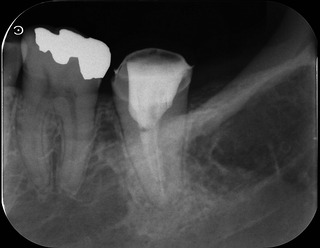

治療前 治療後

なんとか骨ができてくれています。